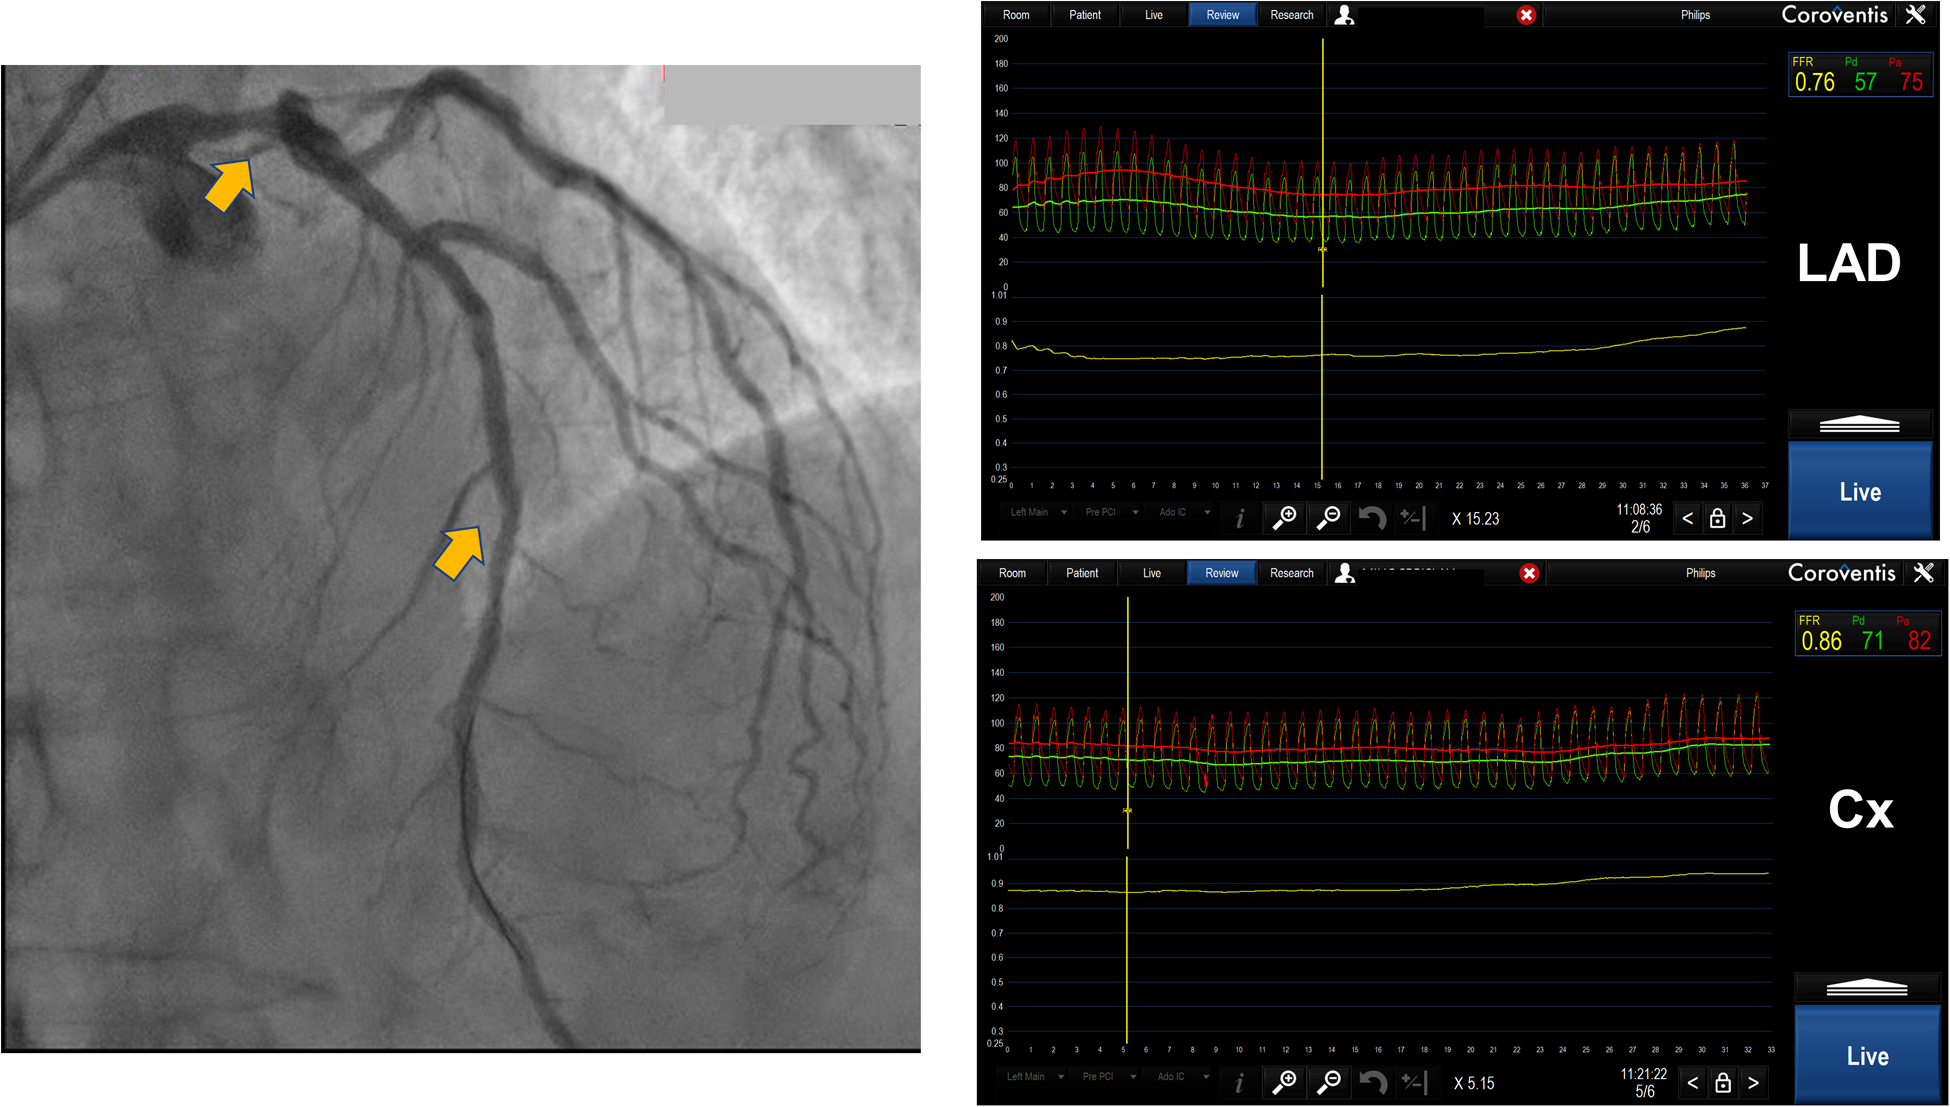

Figure 3

Distal left main lesion evaluation with downstream stenosis in LAD using Coroventis CoroFlow cardiovascular software (Coroventis AB, Uppsala, Sweden). Placing a pressure sensor in distal LAD FFR 0.76 was acquired while placing a sensor in distal Cx, free from disease, obtained FFR was 0,86. The lesion of distal LM was deemed insignificant.